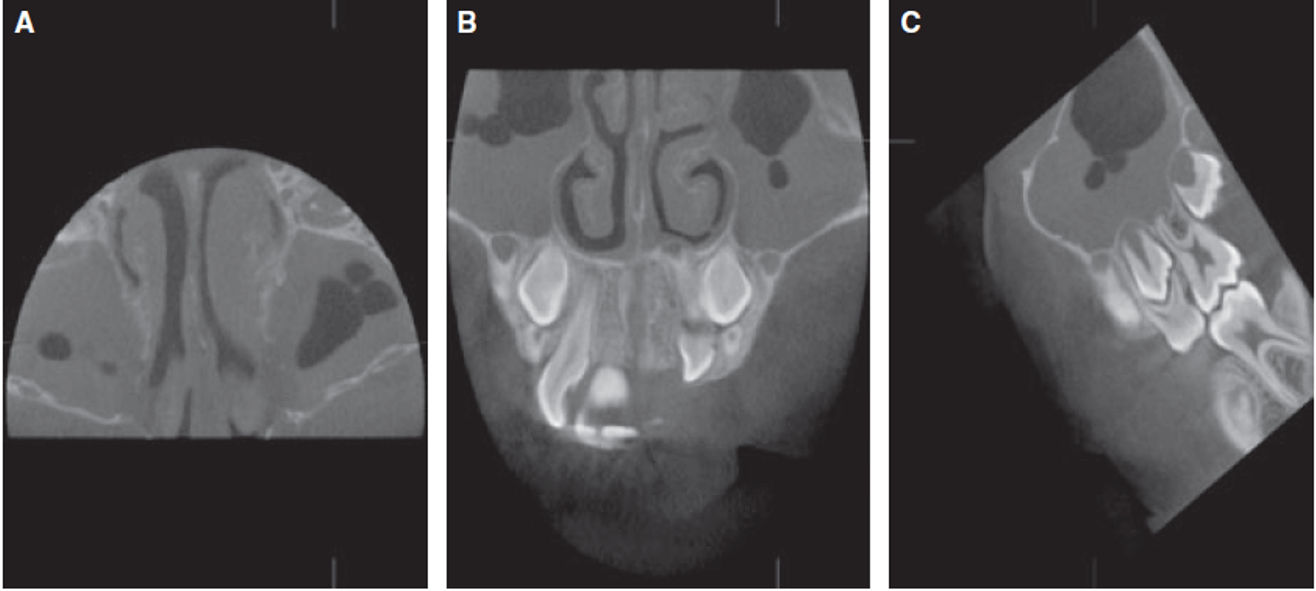

Este estudio muestra que incluso en imágenes TCCB con un campo de visión limitado (4 × 4 / 6 × 6 / 8 × 8 cm), los hallazgos incidentales del seno maxilar están presentes en una alta proporción (46,8 %). Por lo tanto, cuando se utilizan imágenes tridimensionales, no solo deben examinarse las reconstrucciones 3D renderizadas en superficie, sino que todos los cortes TCCB deben ser revisados sistemáticamente en las tres dimensiones (axial, coronal y sagital). Cuando hay hallazgos incidentales, deben interpretarse junto con otros especialistas para evitar la subestimación o sobreestimación de posibles patologías. Los autores fomentan el desarrollo de directrices para el uso y la interpretación de imágenes tridimensionales realizadas con fines ortodónticos.

Fig.3